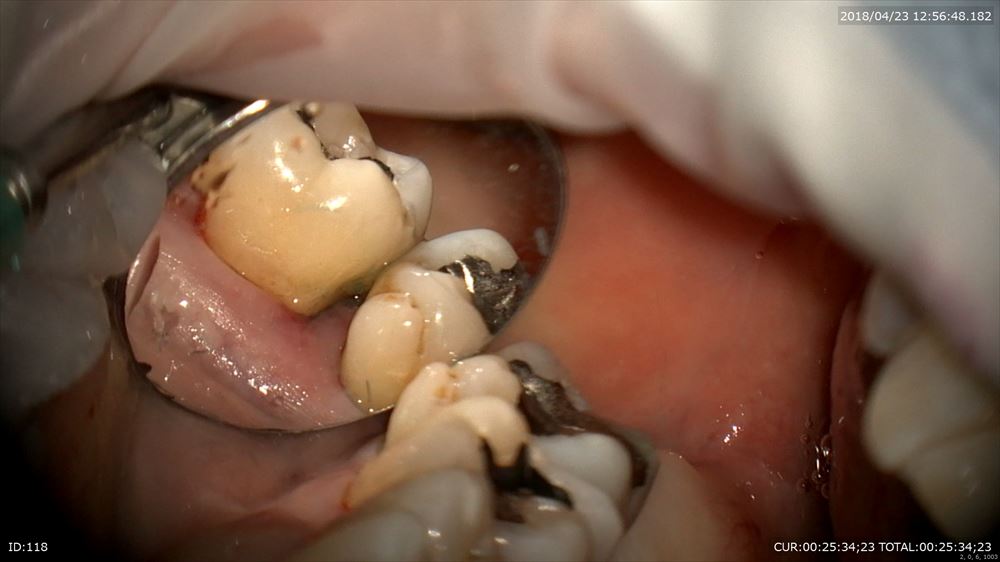

レーザー

こんなにデブライドメントしてもこの様に乳頭も傷をつけず

切り傷などありません。裸眼やルーペとは丁寧さの次元が違います。だから痛くない!!!